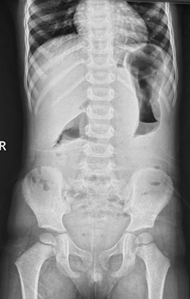

In paralytic ileus, there is too much gas in both small and large bowels (Figure 4 & 5).

Figure 4 Anteroposterior supine abdominal radiograph in a 4-year-old child showing multiple dilatated bowel loops scattered throughout the abdomen haphazardly with presence of gas in the rectum suggestive of paralytic ileus.

In paralytic ileus there is uniform dilatation of bowel to the level of the rectum (Figure 4 & 5).

In paralytic ileus, there are few and less dilated air fluid levels scattered throughout the abdomen (Figures 4 & 5).

In paralytic ileus, the loops are scattered disorderly throughout the abdomen (Figures 4 & 5).